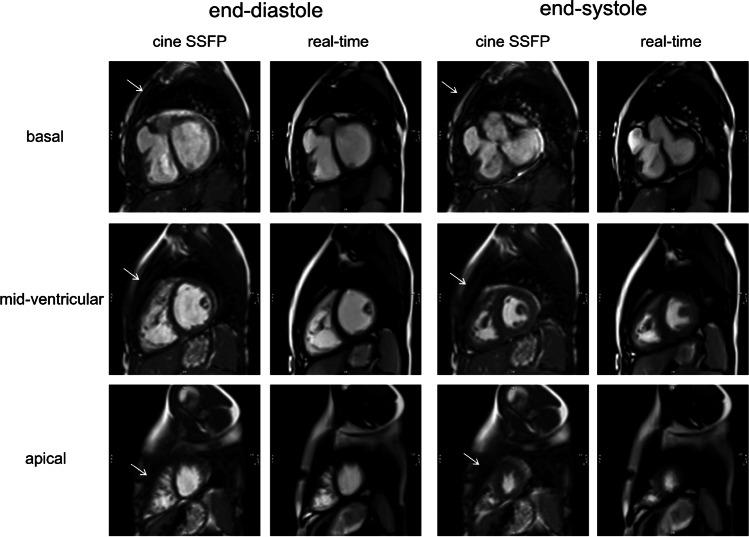

To demonstrate the feasibility of quantitative analysis of cardiac free-breathing RT-MRI and to compare image quality and volumetry during free-breathing RT-MRI in pediatric patients to standard breath-hold cine MRI.

Pediatric patients (n = 22) received cardiac RT-MRI volumetry during free breathing (1.5 T; short axis; 30 frames per s) in addition to standard breath-hold cine imaging in end-expiration. Real-time images were binned retrospectively based on electrocardiography and respiratory bellows. Image quality and volumetry were compared using the European Cardiovascular Magnetic Resonance registry score, structure visibility rating, linear regression and Bland-Altman analyses.

Additional time for binning of real-time images was 2 min. For both techniques, image quality was rated good to excellent. RT-MRI was significantly more robust against artifacts (P < 0.01). Linear regression revealed good correlations for the ventricular volumes. Bland-Altman plots showed a good limit of agreement (LoA) for end-diastolic volume (left ventricle [LV]: LoA -0.1 ± 2.7 ml/m, right ventricle [RV]: LoA -1.9 ± 3.4 ml/m), end-systolic volume (LV: LoA 0.4 ± 1.9 ml/m, RV: LoA 0.6 ± 2.0 ml/m), stroke volume (LV: LoA -0.5 ± 2.3 ml/m, RV: LoA -2.6 ± 3.3 ml/m) and ejection fraction (LV: LoA -0.5 ± 1.6%, RV: LoA -2.1 ± 2.8%).

Compared to standard cine MRI with breath hold, RT-MRI during free breathing with retrospective respiratory binning offers good image quality, reduced image artifacts enabling fast quantitative evaluations of ventricular volumes in clinical practice under physiological conditions.